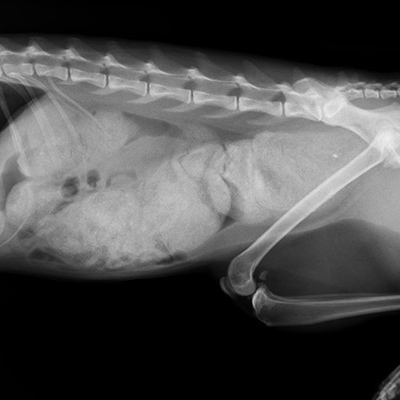

猫の便秘症(死に至る巨大結腸症)

猫の便秘症は死に至る病です。左のレントゲン写真のお腹の中の白い塊が、全てウンチです。便秘を放置してこうなりました(右は正常の写真)。ここまでウンチが詰まると、手術をして腸を切除します。ウンチの硬い猫は、直ちに治療してください。